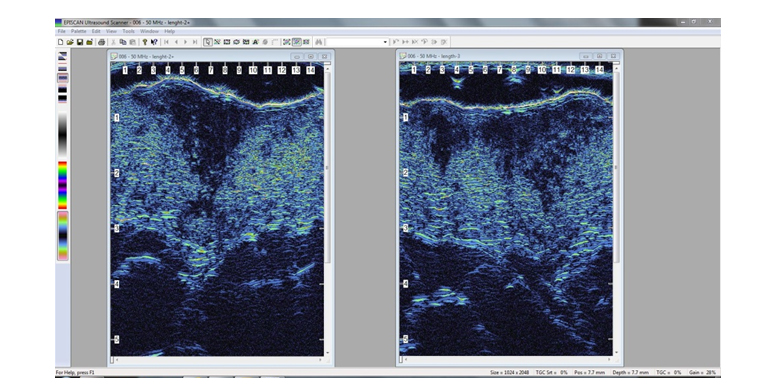

This EPISCAN utilizes broadband ultrasound at frequencies from 20 to 50MHz to image the skin and underlying soft tissue. The system is primarily digital in design, enabling flexible and cost effective data processing and presentation.

EPISCAN Screen showing two images of skin lesions